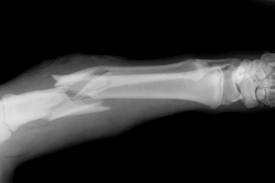

被打伤的医院保卫科干事王先生

据医院介绍,目前5名伤者中,4人在四川省人民医院救治,1人在成飞医院观察。受伤人员多为轻型脑外伤、头皮血肿等,但两名伤情较重者分别为轻度肾挫伤、血尿,以及闭合性腹部损伤,不排除迟发性脏器损伤。两名伤情较重者已经收入四川省人民医院急诊外科住院治疗。